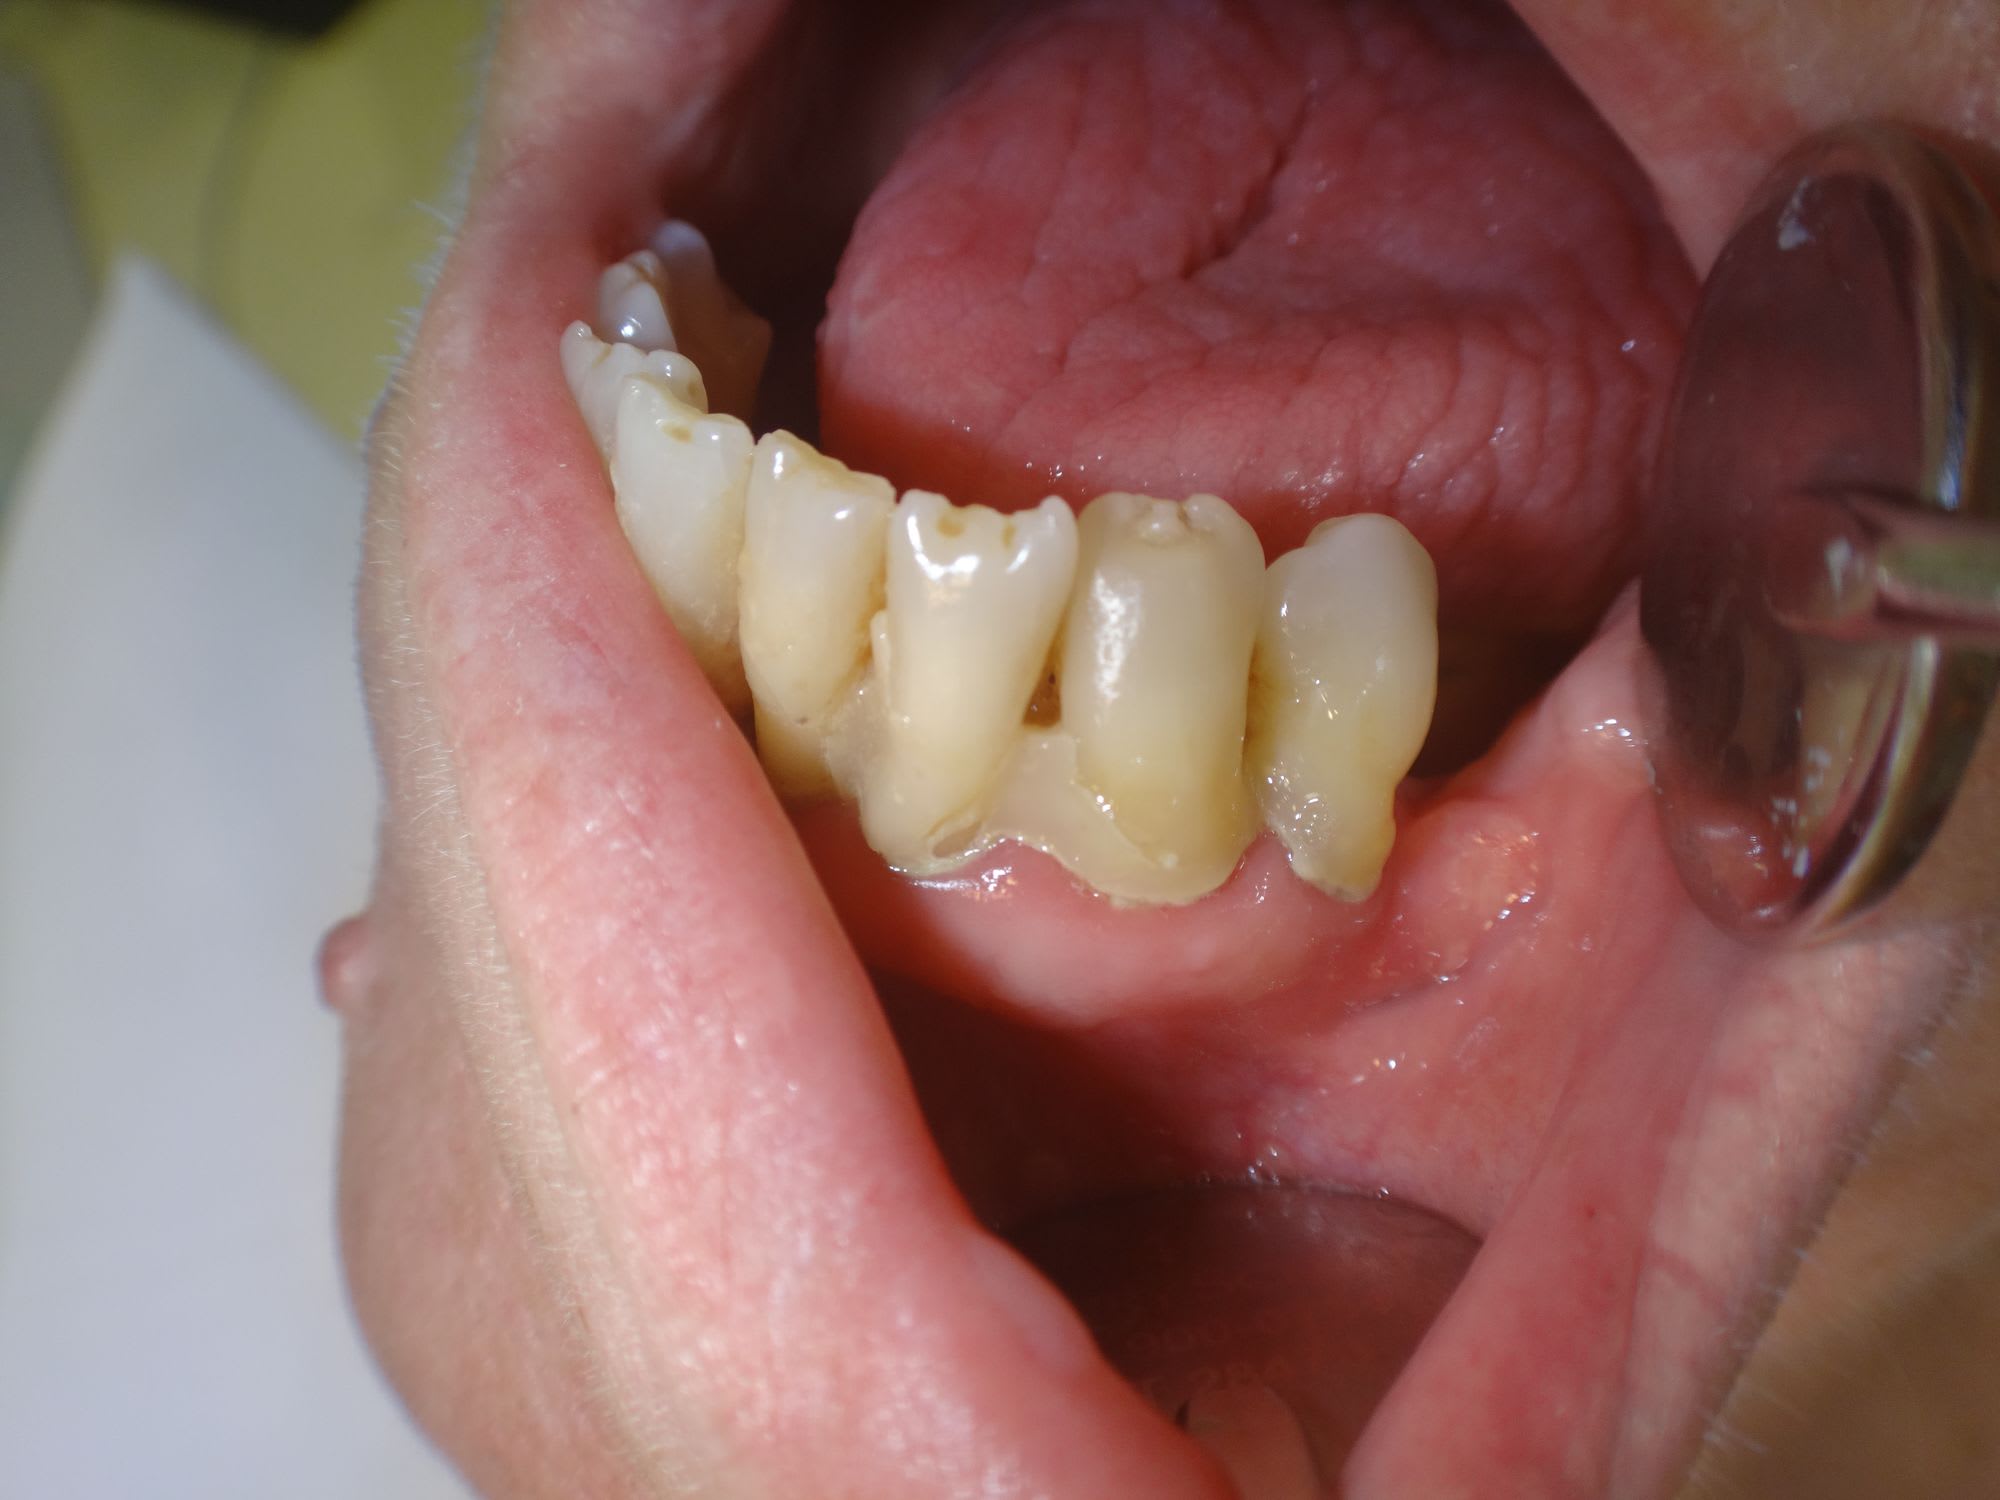

Des composites pour boucher des triangles noirs et des classes 2 à l'amalgame